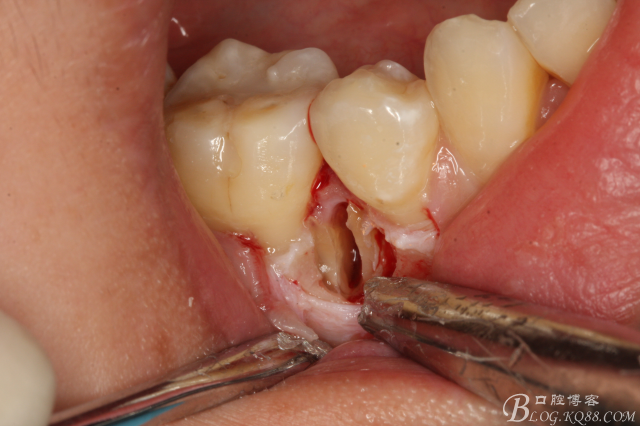

圖12.微創(chuàng)牙挺放入制備好的溝槽內(nèi)。

圖13.取出一塊牙根。給余留 牙根騰出脫位空間

圖14.緩慢在余留牙根周圍用挺,挺松45余留牙根